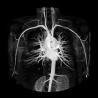

Darstellung der Schlagadern ohne Katheter, Jodkontrastmittel oder Röntgenstrahlen